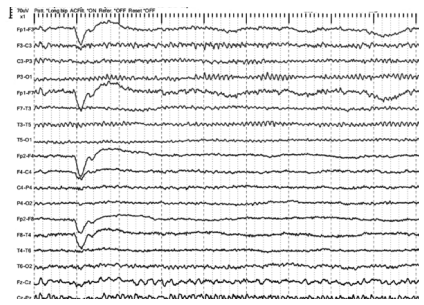

Assinale a alternativa abaixo que indica um possível diagnóstico para o traçado a seguir

(sensibilidade = 7 uV/mm).